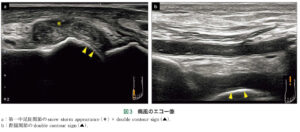

| 検査 | 【血液検査】 55歳未満の場合は二次性(4H)を否定するためCa、P、Fe、Mg、ALPを確認 【画像検査】単純X線:関節軟骨の線状石灰化像、関節裂隙に層状石灰化 ※画像所見があっても結晶誘発性関節炎と診断できるだけでCPPD症とは限らない エコー:膝関節の硝子軟骨内に石灰化を認めればCPPD症を疑う頸部CT:crowned dens syndromeの場合、軸椎歯突起後方の環椎横靱帯の石灰化所見が見える。 【関節穿刺】 急性期に穿刺し、関節液を偏光顕微鏡で観察し、方形・棒状の結晶を確認(確定診断) ※ただし、化膿性関節炎や関節リウマチなどに合併することもあるため慎重に診断すべし |

【画像検査】

エコー:膝関節の硝子軟骨内に石灰化を認めればCPPD症を疑う